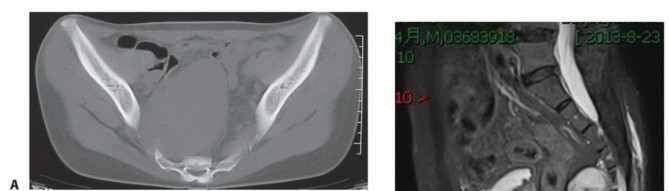

التصوير المقطعي المحوسب والرنين المغناطيسي

- التصوير المقطعي المحوسب (CT): يُعد بتقنية التباين الوريدي الأسلوب الأمثل لتقييم مدى انتشار الورم في العظم وتدميره، والتكلسات المحتملة، والموقع التشريحي، والإمداد الدموي، وعلاقة الورم بالأعضاء الحشوية. يساعد في التفريق بين الأورام الحميدة والخبيثة.

- التصوير بالرنين المغناطيسي (MRI): بتقنية التباين، يُعد حاسمًا لتصوير الأنسجة الرخوة ومدى انتشار الورم فيها، وعلاقته بالأنسجة المحيطة (مثل الأوعية الدموية والأعصاب والعضلات والأعضاء الحشوية). يُعتبر الأسلوب الأمثل لتصوير الأنسجة الرخوة نظرًا لقدرته الفائقة على التمييز مقارنةً بالتصوير المقطعي.